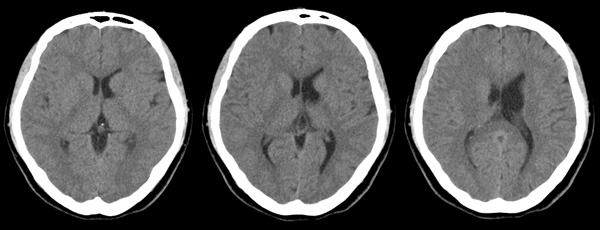

f24y打架后头疼3天,5mm薄扫

左侧侧脑室体三角形扩大,其外上方一小凹陷,左顶部脑沟稍宽,考虑脑裂畸形。

ct所见:左侧顶叶近侧脑室体部处示斑片状低密度灶,同侧脑室扩大,脑沟及脑裂增宽。颅骨结构完整。

诊断:符合脑软化灶,可以结合以往病史进行临床分析,如新生儿时的脑缺氧、血管畸形、后天性的各种原因引起的缺血缺氧、陈旧性的外伤等。由于部分容积效应的原因,左侧脑实质的低密度灶看似与侧脑室相通,必要时可以作mr检查以鉴别有无脑穿通畸形的可能。该病灶与此次外伤无关。

左侧侧脑室息室,属于脑穿通畸形的一种

左侧侧脑室憩室,属于脑穿通畸形的一种,这样描述最准确!